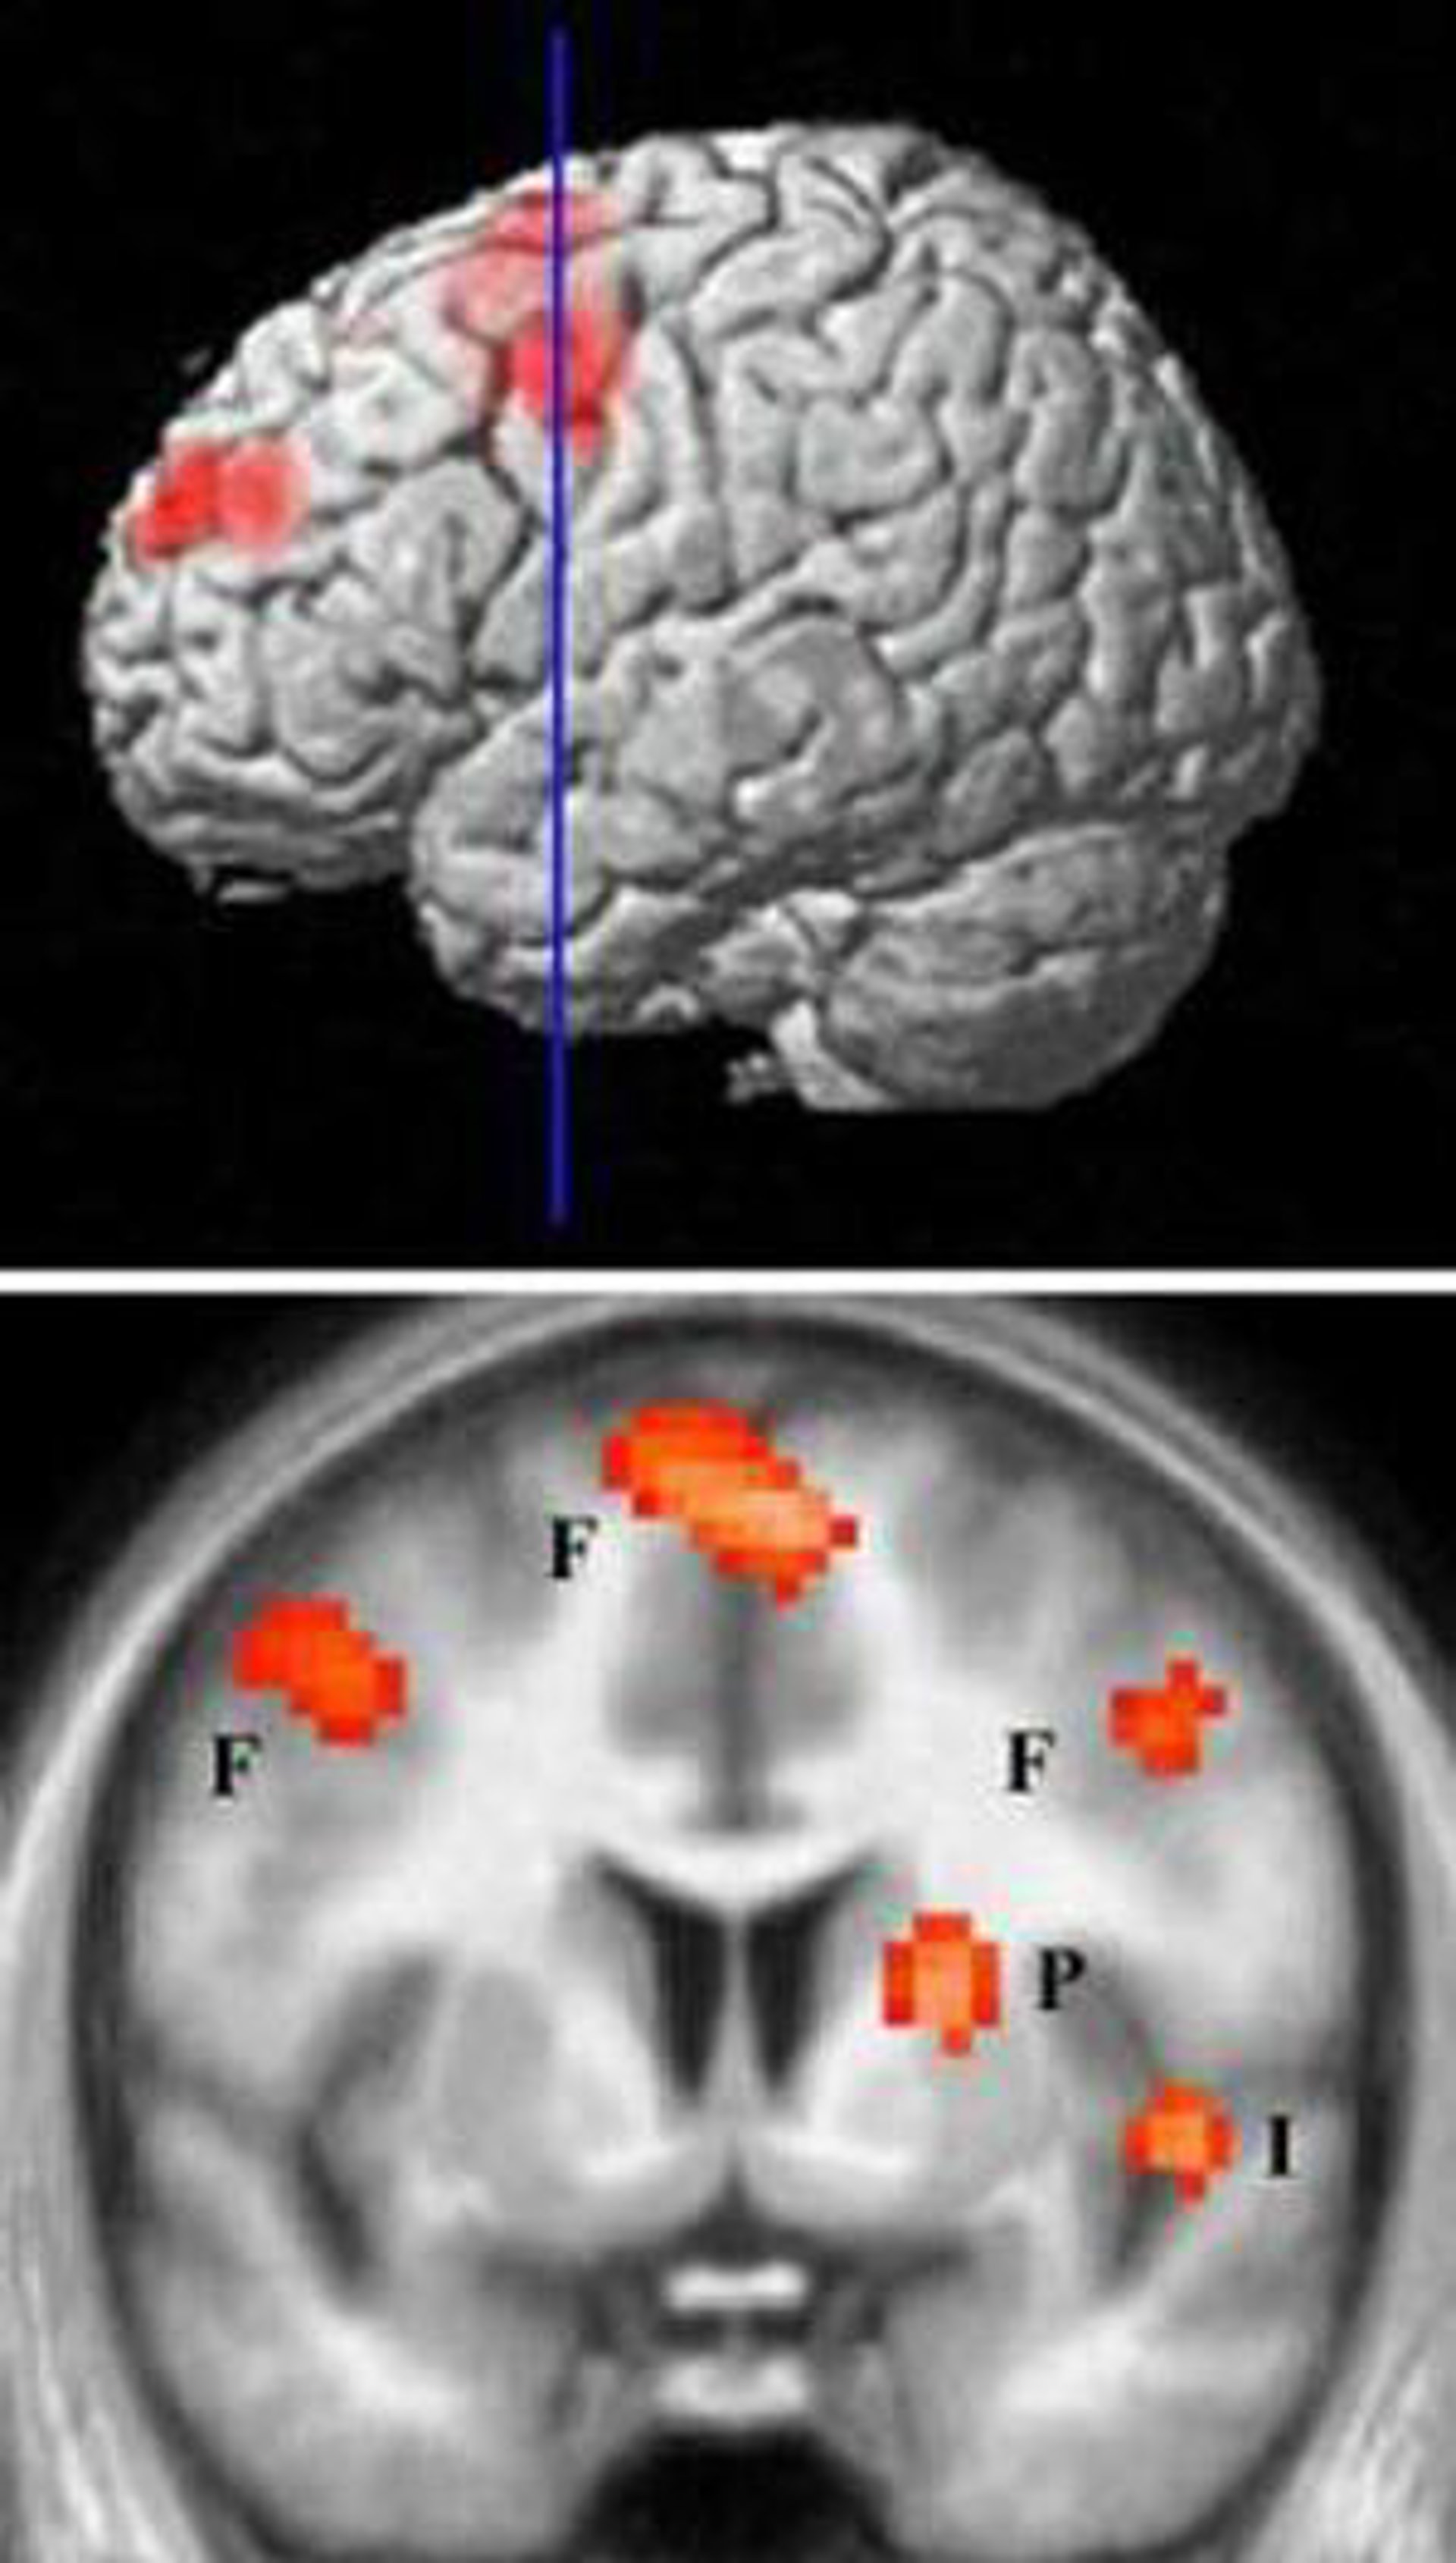

Investigadores del Instituto de Investigación Farmacológica Mario Negri en Milán (Italia) han descubierto que un mecanismo de señalización celular conocido por su participación en las respuestas de defensa inmune también interviene en la epilepsia. El descubrimiento, que se publica en la edición digital de la revista 'Nature Medicine', podría ser útil para el desarrollo de nuevos agentes anticonvulsivos.

La inflamación cerebral es el principal factor en la epilepsia, pero no se conoce bien el impacto sobre la enfermedad de moléculas inflamatorias específicas. Los investigadores, dirigidos por Anna Maria Vezzani, utilizaron varios modelos de epilepsia en ratones y descubrieron que la liberación de una molécula llamada HMGB1 de las neuronas y de la glia y su interacción con un receptor clave de la respuesta inmune contra los patógenos, el TLR4, promovía los ataques epilépticos.

Los investigadores también descubrieron que al bloquear la acción de HMGB1 y TLR4 disminuía la frecuencia de los ataques. Los ratones que carecían de TLR4 eran también resistentes a las manipulaciones que inducen ataques.

Por último, los mayores niveles de HMGB1 y TLR4 en el tejido epileptogénico de pacientes apuntaban a la posible relevancia en humanos de este mecanismo, que podría convertirse en el objetivo de nuevos agentes anticonvulsivos.